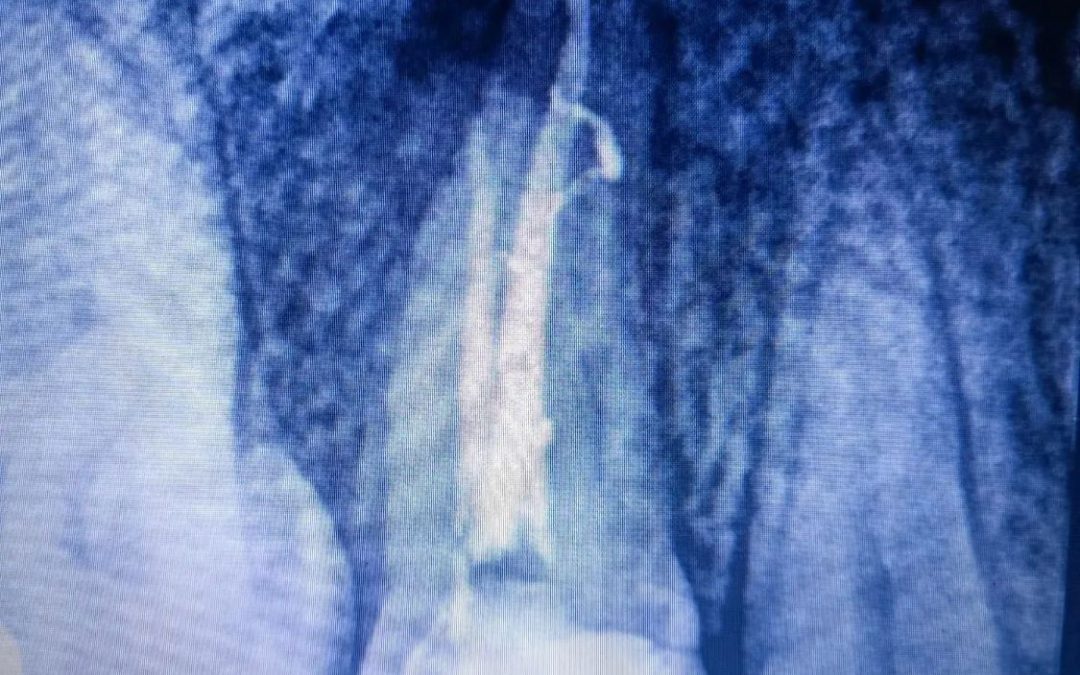

La utilización del Microscopio Electrónico en la realización de tratamientos de Conductos Radiculares, en aquellas piezas dentales que queremos Salvar, nos aportan una seguridad y una predictibilidad importante en la obtención de excelentes resultados finales. Un buen...

🔶 Esta semana os presentamos este caso interesantísimo en el que se consigue salvar este premolar de una extracción casi segura. 🦷 Pulpitis en pieza 1.5 provocada por una reconstrucción filtrada. Realizamos tratamiento de conductos de dicho premolar dando como...